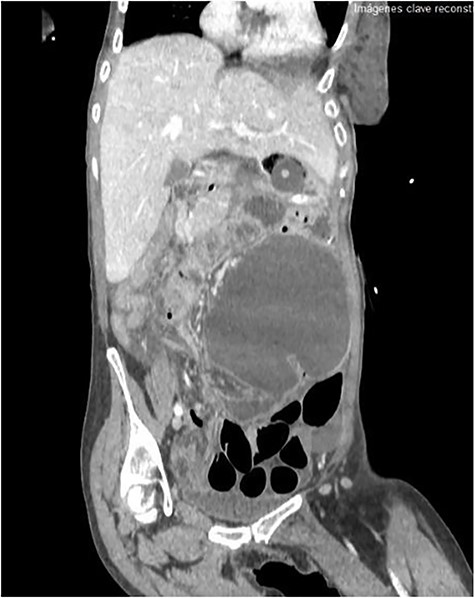

The emergency blood test showed a normochromic and normocytic anemia with an hemoglobin of 10.1 mg/dl and a leukocytosis of 11.150/ul with 70% neutrophils. The abdominal radiography showed a prominent dilation of a small bowel loop. The CT scan reported an 18-cm dilated loop. The main diagnostic suspicion was a small bowel volvulus without signs of ischemia or perforation (Figs 1–3).

However, abdominal radiographs and soluble contrasts have been relegated in favor of computed tomography. This image has a sensitivity close to 100% and a specificity of 90%. Furthermore, it allows the observation of indirect signs of complications such as necrosis or perforation [3].